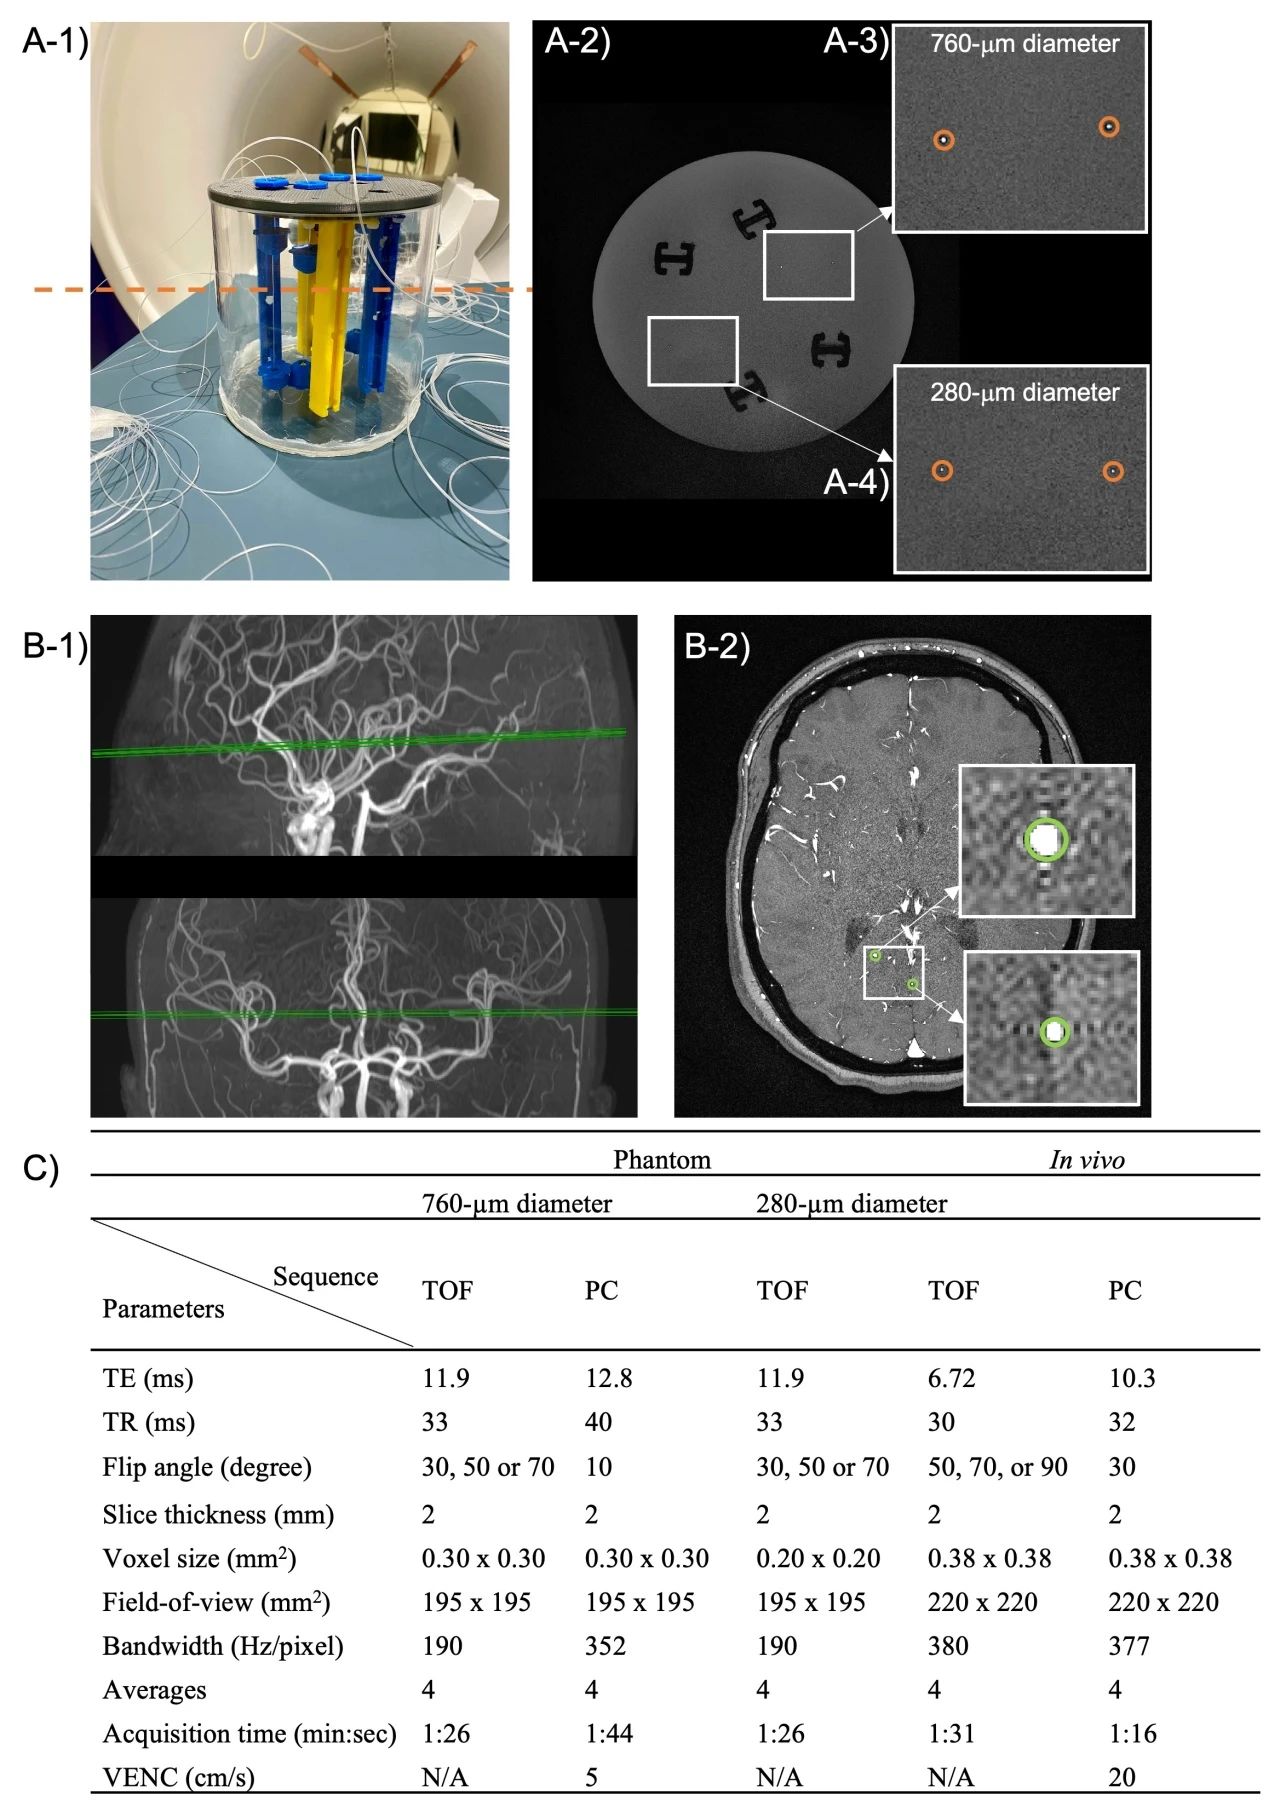

所有实验均在一台3T PET-MR(正电子发射断层成像-磁共振成像)扫描仪上进行,该扫描仪配备了一个32通道线圈。A-1): 使用3D打印材料制成的水填充流动体模,以及两组狭窄管道(直径分别为760和280毫米)。将蒸馏水(掺杂了氯化钠和加多维司特)泵入管道中以模拟血流。虚线指示A-2)中TOF(时间飞行)图像的切片位置。B-1): 体内TOF扫描的切片位置。B-2) 分析了两条脑内血管。C) TOF和PC(相位对比)MRI(磁共振成像)采集参数的表格。